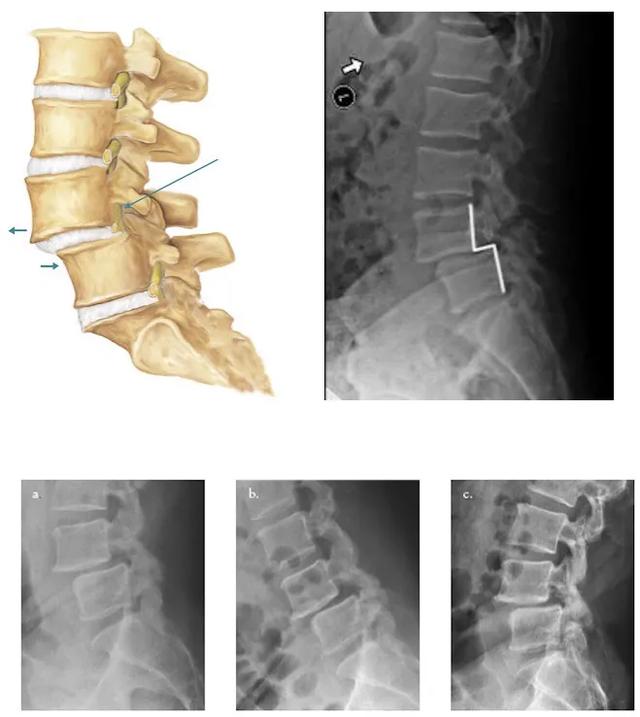

看滑脱的程度。椎体滑脱分为轻度中度和重度。有向前、向后和侧面滑脱。通常向前较多。因为腰椎的曲度是向前的

腰椎滑脱就是两个椎体结构发生改变。上位椎体与下位椎体表面部分或者全部滑脱。也就是腰椎前后肌肉前挡不住后拉不住。滑脱分真性滑脱、假性滑脱。一般滑脱都是一种轻度的滑脱。轻度的就所谓是一度滑脱。腰椎滑脱未引起明显症状。如腰痛、腿痛。可通过锻炼腰背部核心肌肉力量稳定腰椎。锻炼方法有平板支撑。竖脊肌的锻炼;小燕飞可锻炼腰背部及上半身核心肌肉。游泳可锻炼腰背部核心肌肉。拱桥锻炼:平躺在床上。把臀部向上拱起。拱起的高度不用太高。只用轻轻的离开床面就可以。每一次要坚持10秒钟也会对腰椎滑脱有一定作用。如果拍片后显示达到了二度滑脱。甚至二度以上的滑脱。这个时候就会逐渐出现症状。甚至会引起下肢严重的神经症状。最常见的就是。腰痛、无力、跛行等等。最好就医治疗。由医生根据您的情况选择合适的治疗和锻炼方式。以免加重病情。